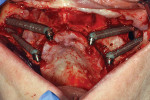

Variations of incorporating zygomatic implants into the severely resorbed maxilla may be part of a conventional type of All-on-4 treatment procedure when sufficient bone exists in the paranasal region for the placement of anterior implant fixtures (Figure 7 through Figure 10). When the paranasal region will not accommodate implant placement, this approach can be expanded to the quad zygoma procedure where two zygomatic implants are inserted in each upper quadrant bilaterally (Figure 11 through Figure 16).18,19

Zygomatic implants are not limited to use in fully edentulous cases. Options exist for partially edentulous patients exhibiting multiple posterior tooth loss with both horizontal and vertical bone loss volume in the ridge crest. The implants may be used in the partially edentulous maxilla when insufficient volume of bone is present as an alternative to osseous grafting of the sinus or crest to enable implant placement in the posterior (Figure 17 through Figure 19). The incorporation of sinus grafting will lengthen treatment time, as the graft will need to mature prior to implant loading if the implant is able to be placed at the time of sinus augmentation. Should the implant not be able to be placed when sinus augmentation is performed, treatment time is further increased and restoration may not be possible for up to 1-year post initial surgery.

Other potential complications that have been reported include oroantral fistula formation, temporary deficit of sensory nerves, vestibular cortical fenestration, postoperative periorbital/subconjunctival hematoma or edema, and moderate nasal bleeding for 1 to 3 days.28 Patients with pronounced buccal concavities of the lateral aspect of the maxillary sinus may be more prone to such complications especially when a non-guided surgical approach is used. The limited intraoperative visibility along with the anatomical complexity of the structures and intricacies of the zygoma make this surgical procedure clinically demanding. Increased availability of CBCT, virtual implant planning, and CAD/CAM surgical guide fabrication may potentially greatly decrease complications and make placement less stressful.